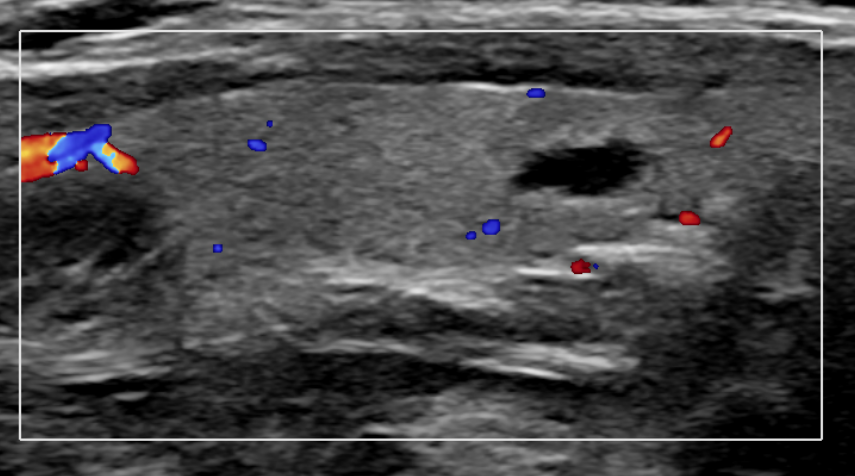

갑상선 낭종의 진단에는 주로 초음파 검사가 사용됩니다. 초음파는 방사선 노출이 없고 안전하기 때문에 널리 활용됩니다.

1) 초음파 검사: 낭종의 위치, 크기, 내부 구조를 파악합니다.